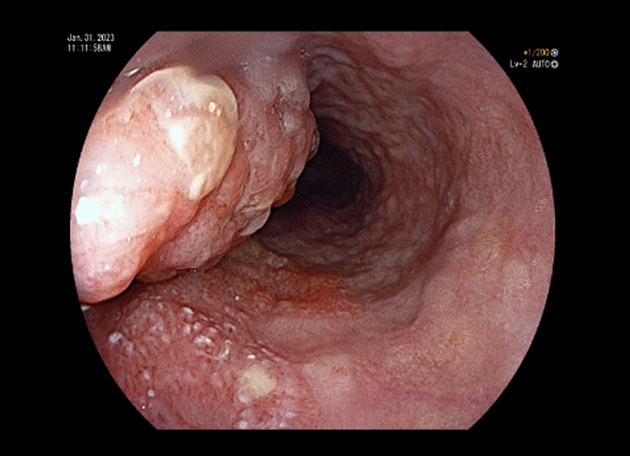

정기적인 위내시경을 받으셨더라면 조기에 발견했을 텐데, 안타까운 경우입니다. 식도암은 음주와 흡연이 가장 중요한 위험인자이며, 특히 흡연량이 많아질수록 위험도도 높아지는 것으로 알려져 있습니다. 음식물 섭취 시 걸린 느낌, 소화장애가 지속된다면 반드시 위내시경 검사를 통해 이상 여부를 확인해 보시기 바랍니다.